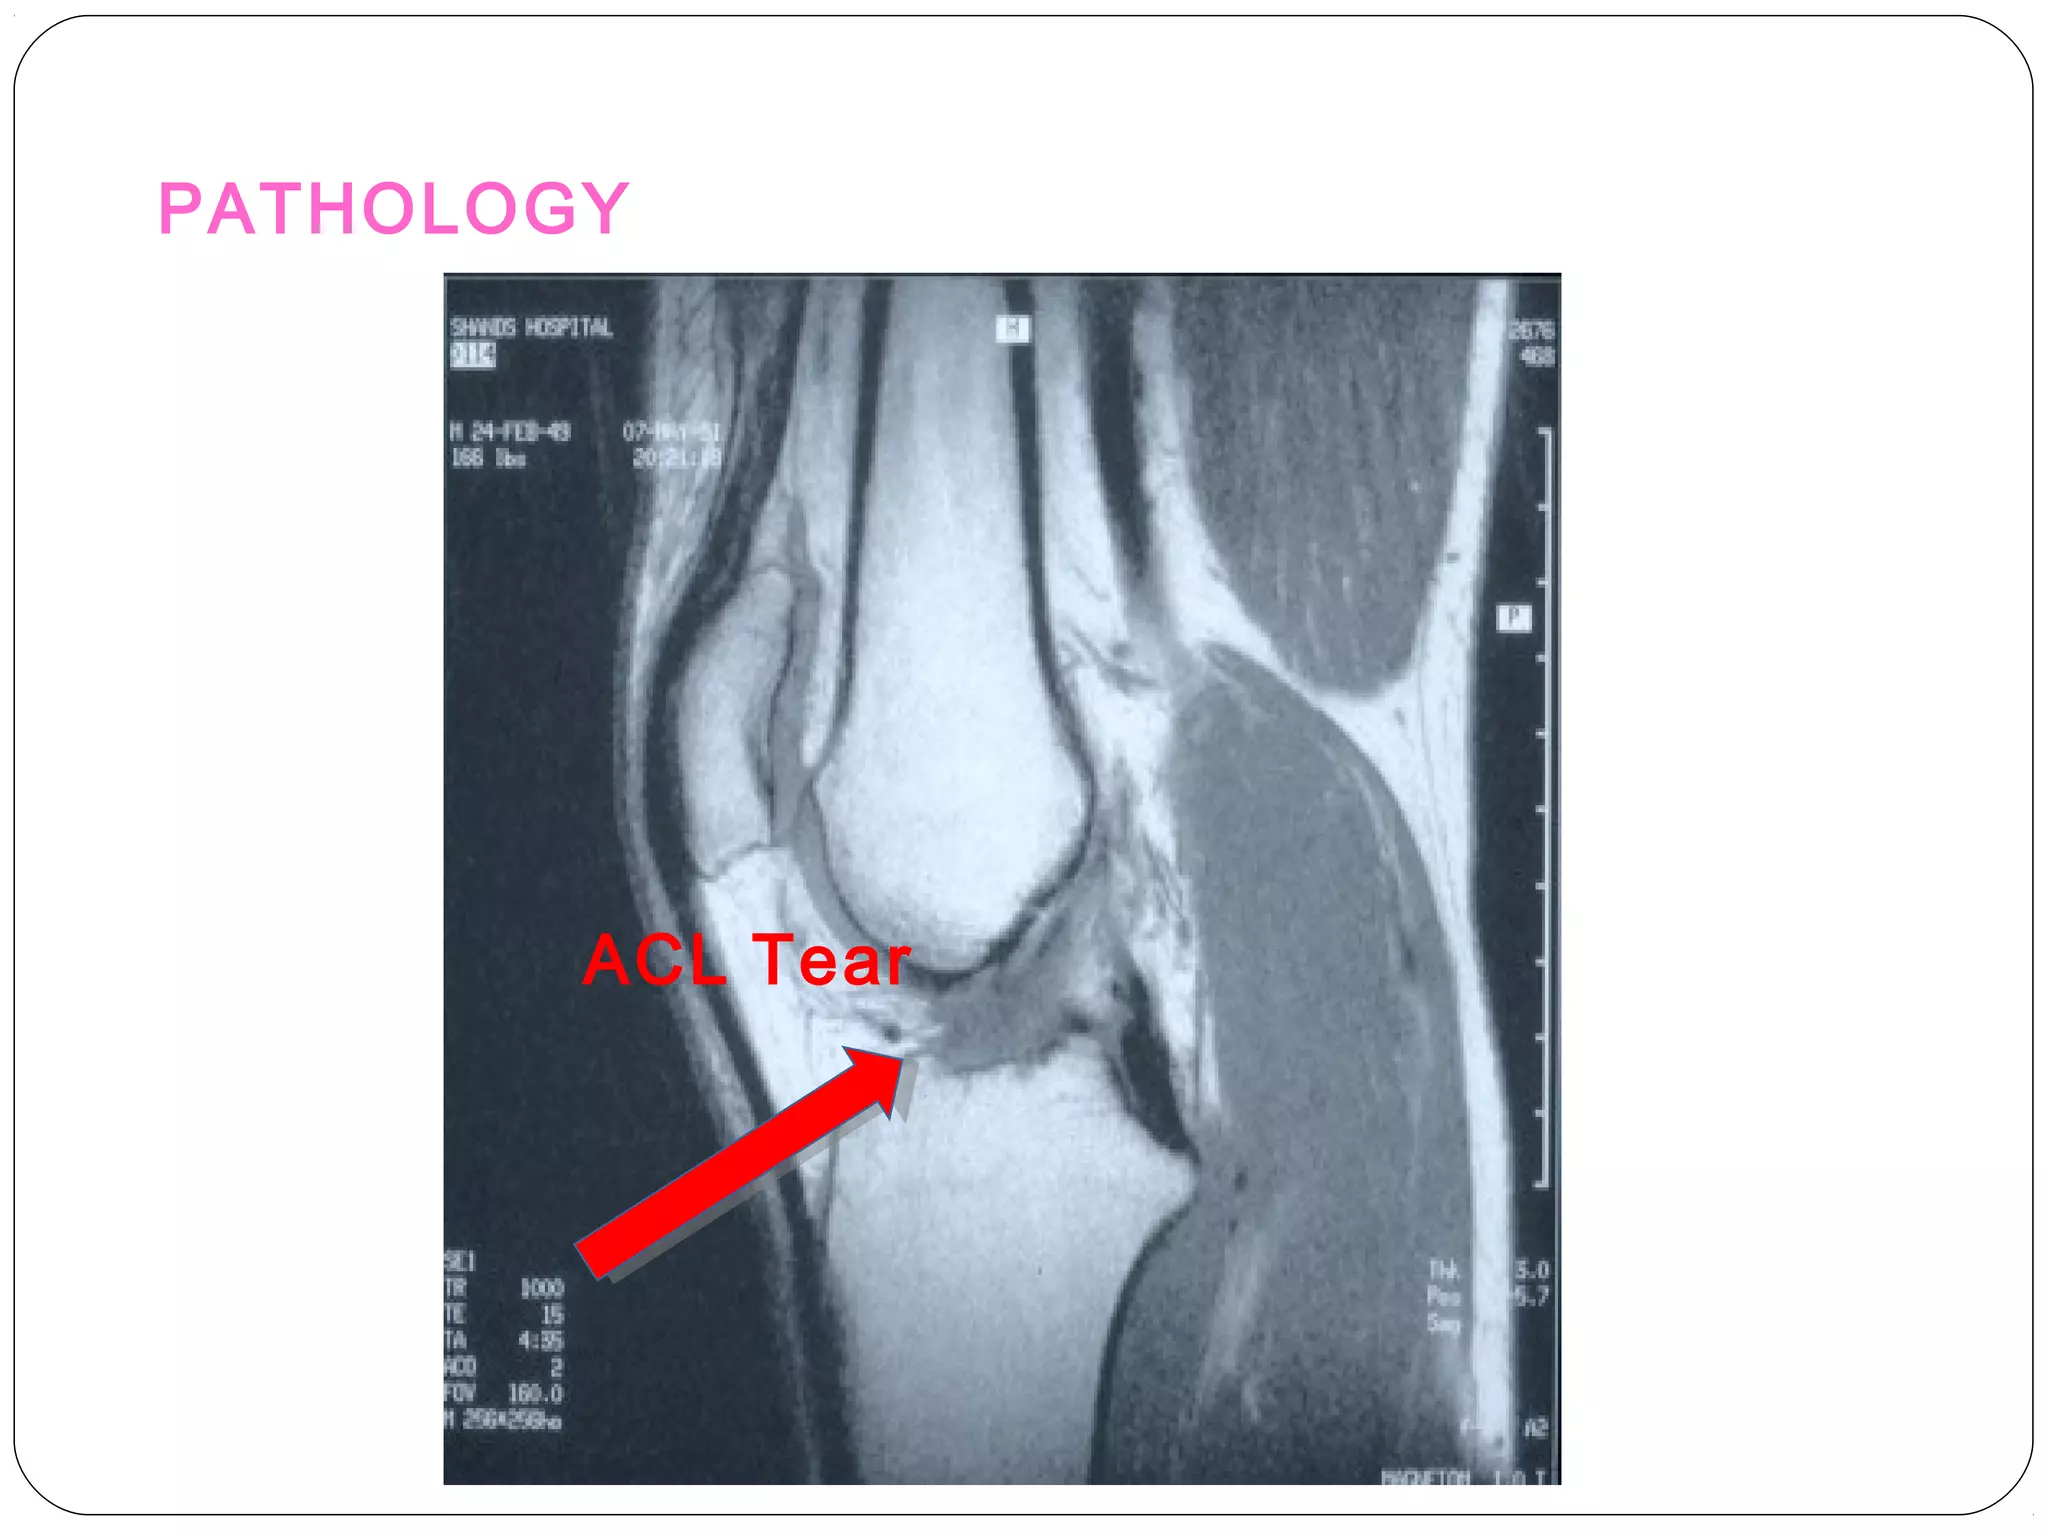

PATHOLOGY

ACL Tear

Knee - MRI Sagittal